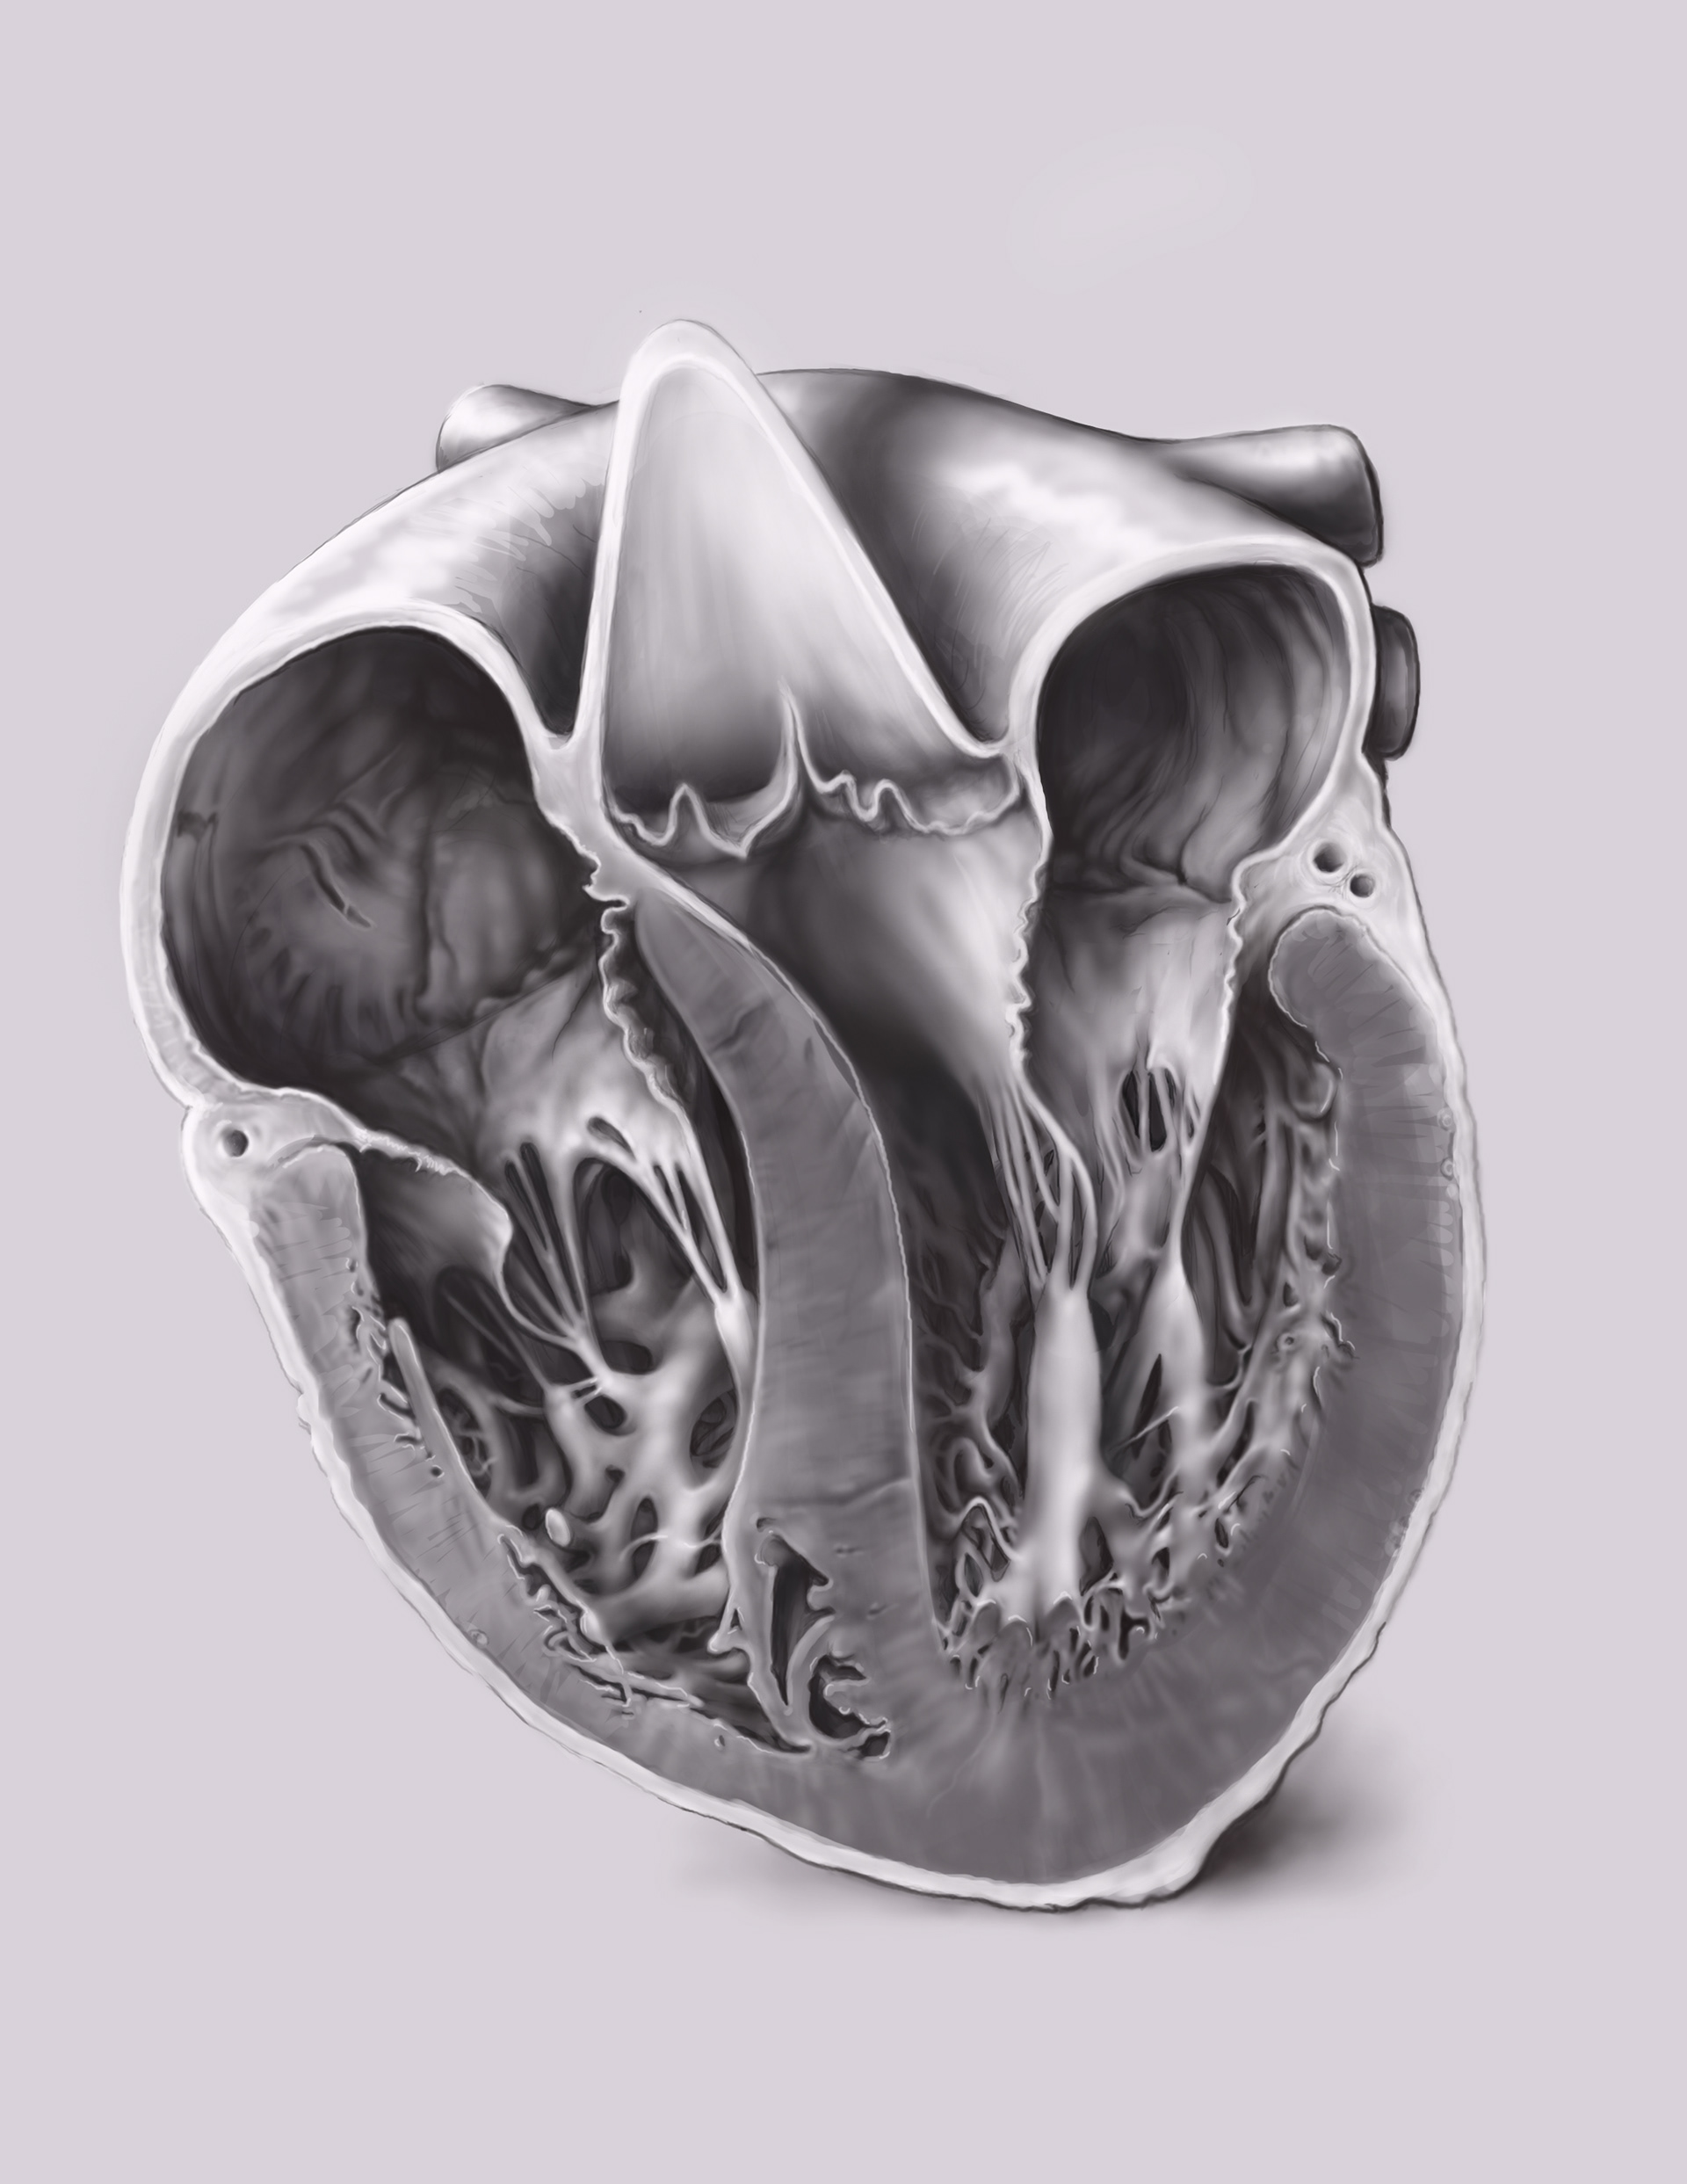

These illustrations were created for a medical app developer, using the direction of the team doctor and scientist. After working together closely to come up with the final designs, my drawings were passed off to the team of animators. My drawings were used as their templates for rendering out 3D digital models and animation. They even developed a virtual reality fly-through to be used on the Oculus Rift-- which was incredible.

Final concept for the slice view of the heart.